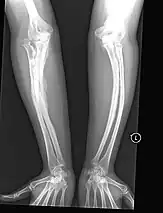

The main symptom of osteogenesis imperfecta is fragile, low mineral density bones; all types of OI have some bone involvement.[5] In moderate and especially severe OI, the long bones may be bowed, sometimes extremely so.[28] The weakness of the bones causes them to fracture easily; a study in Pakistan found an average of 5.8 fractures per year in untreated children.[29] Fractures typically occur much less after puberty, but begin to increase again in women after menopause and in men between the ages of 60 and 80.[1]: 486

- Type V – Having the same clinical features as type IV, it can be clinically distinguished by observing a "mesh-like" appearance to a bone biopsy under a microscope. Type V can be further distinguished from other types of OI by the "V triad": an opaque band (visible on X-ray) adjacent to the growth plates; hypertrophic calluses (abnormally large masses of bony repair tissue) which form at fracture sites during the healing process; and calcification of the interosseous membrane of the forearm,[50] which may make it difficult to turn the wrist.[1]: 429 Other features of this condition may include pulled elbow, and, as in other types of OI, long bone bowing and hearing loss.[64] Cases of this type are caused by mutations in the IFITM5 gene on chromosome 11p15.5.[64][49] The separation of type V from type IV OI, its clinical type, was initially suggested even before its genetic cause was known, by Glorieux et al. in 2000.[50][65] Type V is relatively common compared to other genetically defined types of OI—4% of OI patients at the genetics department of the Brazilian Hospital de Clínicas de Porto Alegre were found to have it.[66]